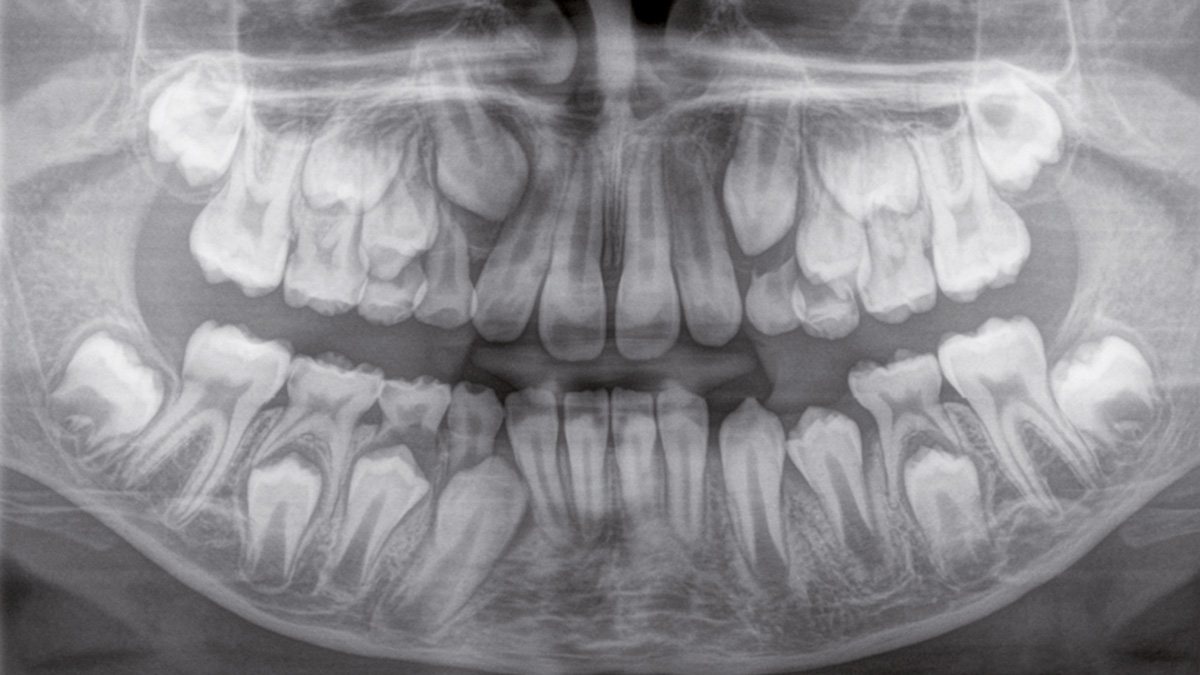

Der Direct Conversion Sensor erfüllt besonders hohe Standards für die 2D-Bildgebung

Der Autofokus erzeugt aus mehreren tausend Einzelbildern automatisch eine beeindruckende scharfe Panorama-Röntgenaufnahme

Der Direct Conversion Sensor (DCS) hat den Standard der Panorama-Bildgebung neu definiert. Röntgenstrahlen werden direkt in elektrische Signale umgewandelt – im Gegensatz zu herkömmlichen Systemen gibt es keinen Signalverlust durch Lichtumwandlung, was eine verbesserte Bildgebung ermöglicht. Das Ergebnis sind Bilder mit einer sehr hohen Schärfe, selbst bei niedriger Dosis.

Eine Röntgenaufnahme muss sofort diagnostizierbar sein. Der Autofokus hilft dabei erheblich. Orthophos SL erfasst mehrere tausend Einzelbilder in einem Zyklus und erkennt automatisch scharfe Bereiche, um ein gleichmäßig scharfes Gesamtbild zu erzeugen. Der intelligente Autofokus erfordert keine manuellen Arbeitsschritte vor und nach der Erfassung.